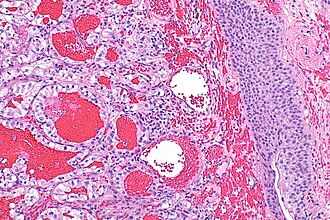

| Caption = Clear cell renal cell carcinoma metastasis to urinary bladder. [[H&E stain]]. | |||

Image: Clear cell renal cell carcinoma metastasis to bladder -- intermed mag.jpg | CCRCC in bladder - intermed. mag. (WC) | |||

Clear cell renal cell carcinoma metastasis to urinary bladder. H&E stain. | |